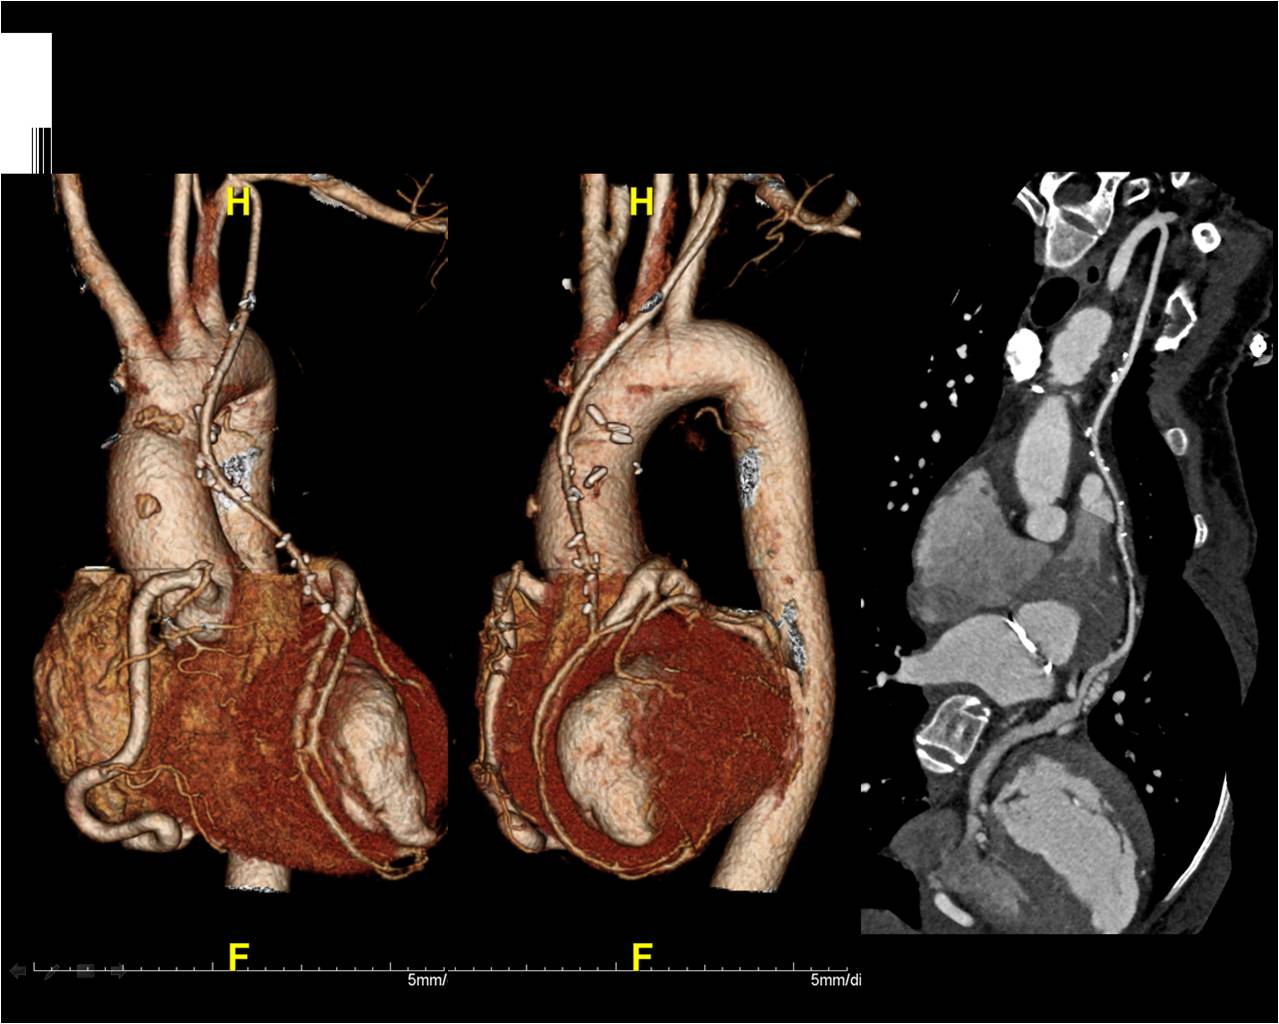

M/49, Severe dyspnea and Jaundice

Heon Lee, Department of Radiology, Soonchunhyang University Hospital Bucheon